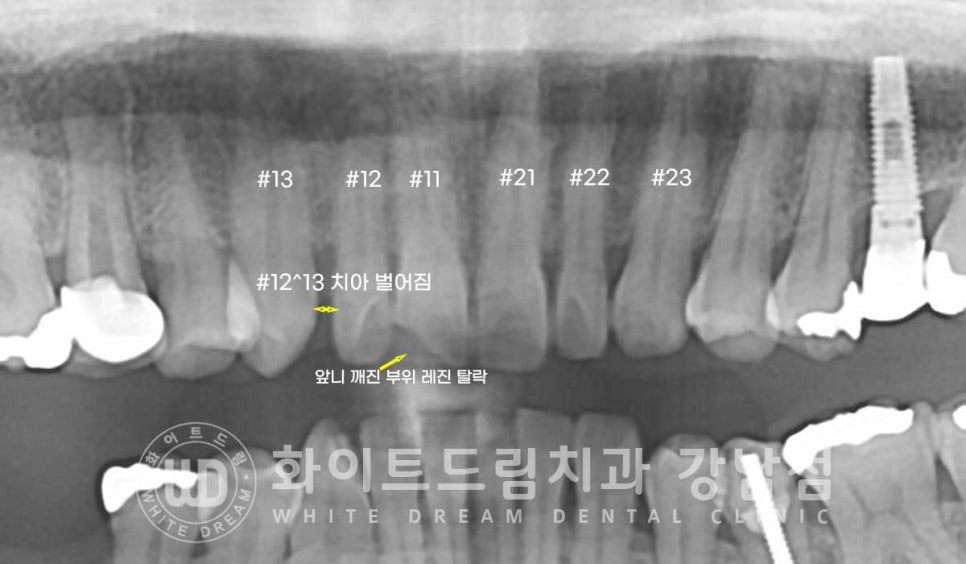

오늘 소개해 드릴 환자분도 큰 앞니 양옆 측절치가 왜소치이신 환자분이셨는데요.

12번 치아와 13번 치아 사이가 크게 벌어져 있어

웃을 때마다 빈 공간이 보인다며 스트레스를 호소하신

40대 여성분이십니다.

환자분의 구내 사진을 보면 작은 측절치 옆으로

빈 공간이 크게 보이는 것이 확인되고, 이 왜소치가 살짝 틀어져있는 것도 확인됩니다.

그리고 11번 큰 앞니 끝부분에 레진 치료를 받으셨는데

이 레진도 치료를 받은 지 오래되기도 했고,

레진으로 치료 범위가 커 파절되어 있는고 치아가 뻐드러진 상태였습니다.